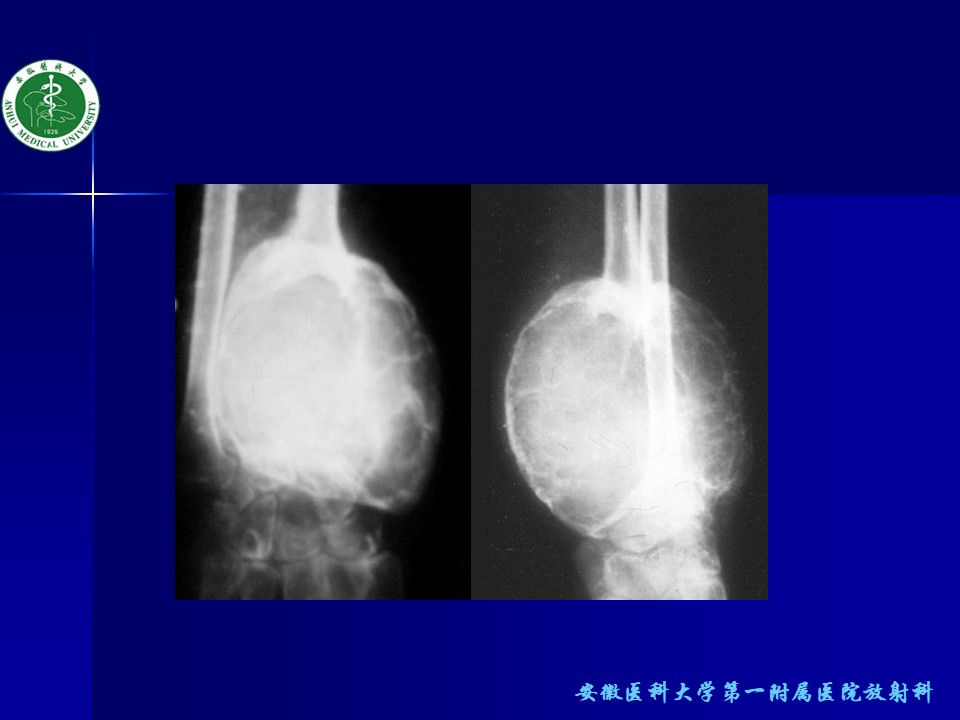

“骨关节良性肿瘤的诊断及鉴别诊断PPT” 的相关文章